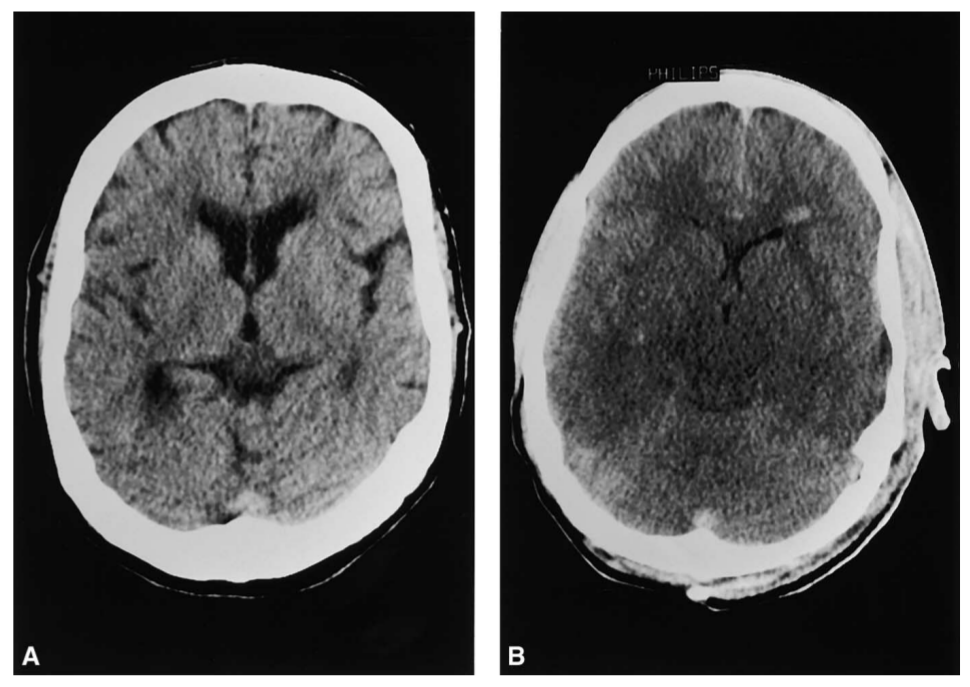

TC de cráneo del mismo paciente eunatrémico (A) y tras desarrollar hiponatremia aguda (B). Se aprecia la desaparición de los surcos y ventrículos, así como la hipodensidad del parénquima, compatible con edema cerebral.

Gross P. Nephlorogy Forum: Treatment of severe hyponatremia. Kidney Int. 2011;60:2417-27. Reproducido únicamente con fines educativos.